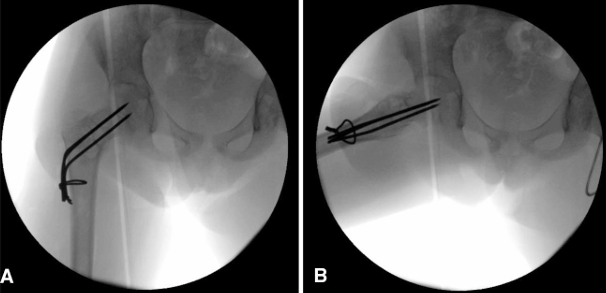

手术技术:经股骨近端外侧入路,逐层分离直至显露骨质。在转子区前侧皮质上使用钻头开窗,保留外侧皮质以用于固定,随后对病灶进行刮除,远端显露股骨髓腔,并取样送病理活检。其后,自外侧皮质向股骨头方向钻入 3 枚直径为 2 mm 的克氏针,至软骨下骨约 5 mm 。随后将克氏针弯曲成较大的弧形,以防止回弹及内翻移位,并加用一根环扎钢丝穿过股骨,以帮助增强稳定性(图 3)。最后,在病灶区域填充异体骨移植材料。切口关闭后,考虑到患儿年龄,予以半髋人字石膏固定 6 周(图 4)。若患者年龄更大且配合度更好,则可不使用石膏固定(见第二个病例)。术后 3 个月,拆除人字石膏并复查影像学检查(图 5)。